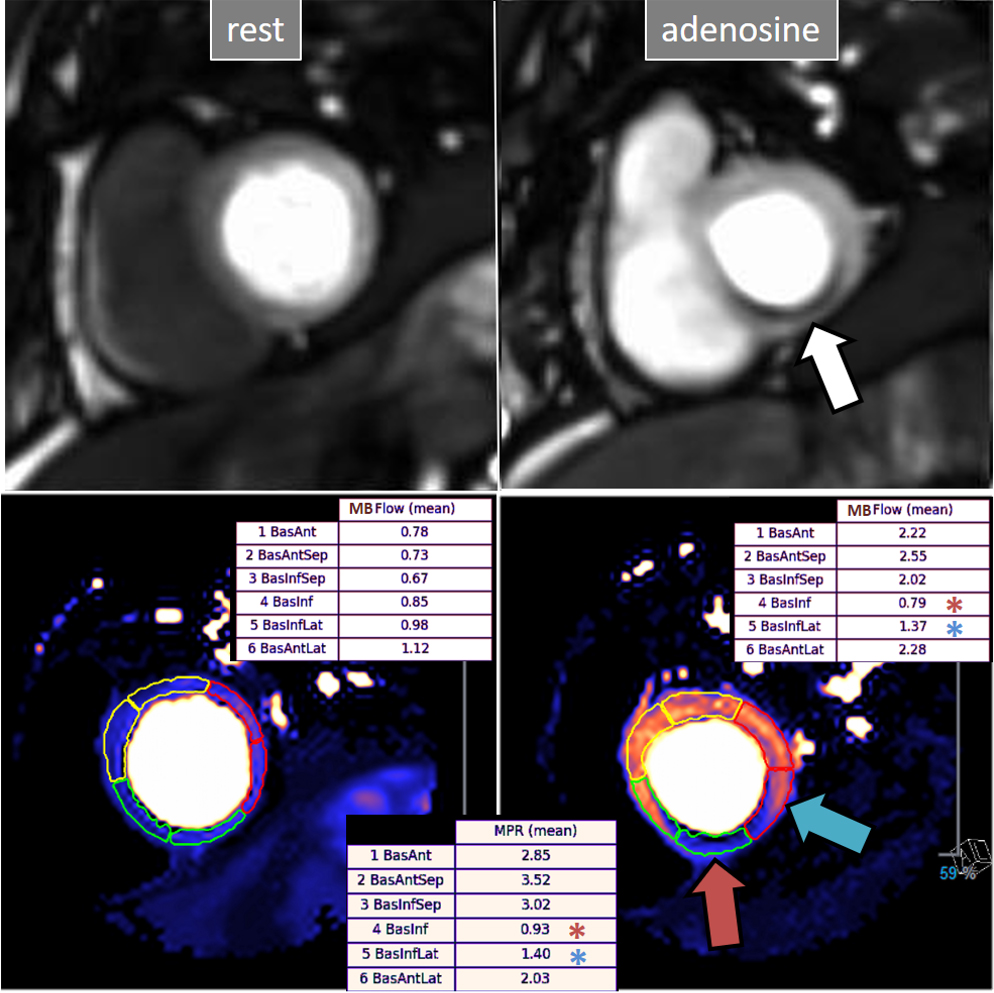

More recently, a new method has been proposed [56] that includes several important solutions contributing to a reliable implementation on the routine workflow of a CMR exam [57]. Firstly, it is based on a dual imaging sequence strategy (Fig. 24), where low-resolution blood pool images used for estimation of the AIF are followed by multi-slice 2D high-resolution myocardial perfusion sequence. The total duration of the scheme is around 500 msec, that allows for the obtention of 3 slices sampled every heart cycle, as long as the heart rate is below 120 b.p.m. AIF extraction from the low-resolution sequence has proven to be reliably obtained automatically [58] (Fig. 25). Second, motion and surface coil intensity correction are applied to both AIF and perfusion images [57, 59]. Third, a process of SI conversion into gadolinium concentration [Gd] units is performed for both sequences [56] (Fig. 26). Fourth, and most important, AIF [Gd] curve and perfusion [Gd] images are inputted into flow mapping step for pixel-wise myocardial flow mapping [57] rendering quantitative values of MBF (in mL/min/g) (Fig. 27). Based on a process of deep learning [60], myocardial segmentation and allocation of flow values are automatically processed (Fig. 28) and integrated into the MRI scanner using the Gadgetron streaming reconstruction software [61, 62]. The final output of the process consists on a bull’s-eye plot of color-encoded MBF values on the LV 16-segment model, and the listed numerical values of absolute flow at stress and at rest and, also, the derived MPR, each of them calculated for the endo- and epicardial halves of the segment (Fig. 29). The presence of inducible perfusion defects is thus detected not only visually on the perfusion color map, but also quantitatively estimated by the absolute values of stress MBF and the corresponding MPR of the involved myocardial segments (Fig. 30). Of note, in case of a suboptimal effect of the vasodilator agent, a lack of increase in stress MFB and MPR values is observed, leading to a potentially false positive diagnosis, in contrast with the visual assessment of perfusion, which, in this case, as stated above, would not show induced defects, with the potential for a false negative.

Fig. 30.QP study in a patient with an inducible defect. A defect at the inferior basal region is detected in the conventional stress perfusion sequence (white arrow). QP maps from the corresponding basal segments show transmural intense reduction of the stress MBF and MPR at the inferior segment (red arrow and asterisks), with less severe involvement of the infero-lateral one (blue arrow and asterisks). Observe the reduced stress MBF in comparison with the rest value of the inferior segment, with a resultant MPR value significantly decreased, inverted actually (0.93), indicating coronary steal phenomenon and, in accordance, probably severe inducible ischemia of the region.